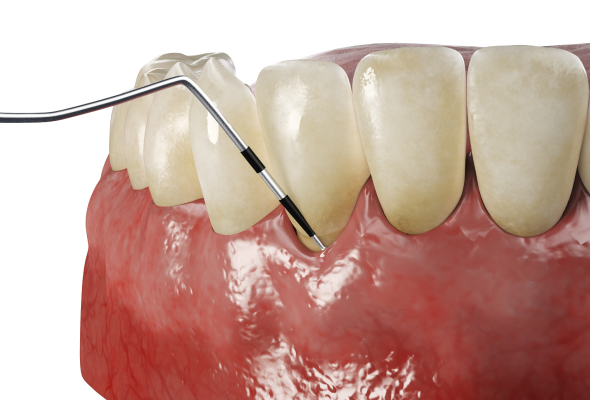

스케일링

초음파 치석 제거 기구를 사용해 치아 머리 부분에 붙어 있는 치석과 플라그를 제거합니다. 통증과 불편감을 최소화해 진행하며, 초기 잇몸질환 예방에 중요합니다.

치근활택술

국소 마취 후 치아 뿌리 표면에 붙어 있는 치석과 염증 조직을 제거하는 치료입니다. 치주염이 진행된 경우 잇몸 염증을 완화하고 질환의 악화를 막는 데 도움이 됩니다.